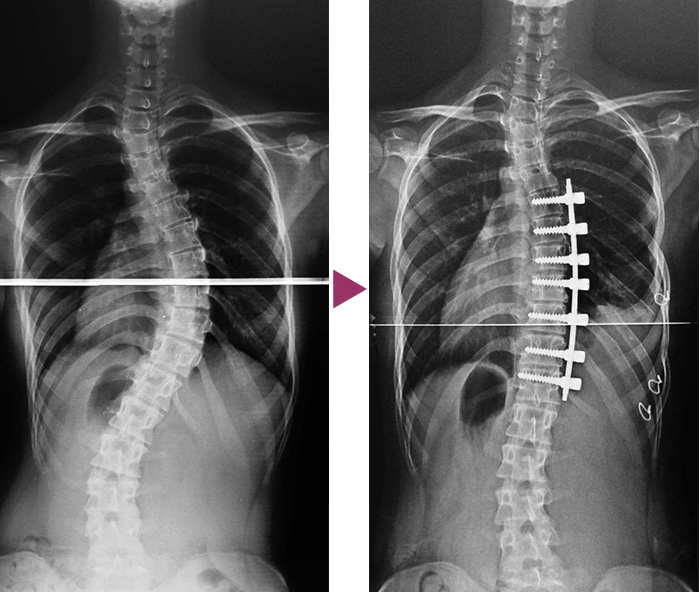

まず、、側湾症とは

背骨(脊柱)が変形し、足の長さや肩の高さ、肋骨の高さが大きく変化する骨の変形です。。

突発性側湾症は放っておくと大人になり、側湾にによる身体の歪みが顕著に残ります。。また症状がひどくなると手術をされる方もいらっしゃいます。。